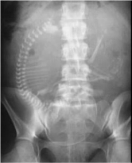

黄老师从世纪之交物理学的三大发现(伦琴发现X射线,贝克勒尔发现天然放射性现象和J·J汤姆孙发现电子)引出今天的讲座主题,X射线和电子的发现都源于对阴极射线的研究,而对X射线的研究又引出了放射性的发现。随后黄老师讲解了X射线的基本特性、X射线的发现过程、结合X射线的独有特征进一步说明X射线的“双刃剑”特征以及X射线在晶体结构分析、元素成分分析、有机物的动力学过程观测、固体材料中微观动力学研究、生物透视与人体透视、考古和宇宙学研究等重要领域的广泛应用。最后黄老师与同学们进行了广泛交流,同学们思维活跃,学术探索热情高涨。